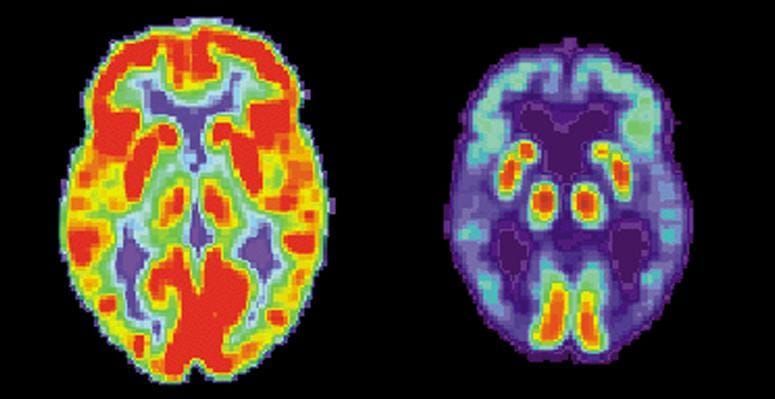

The MRC Toxicology Unit research team, led by Professor Giovanna Mallucci at the University of Leicester, has managed to successfully control the progression of Prion disease, a neurodegenerative disorder, in mice. The study, published in Science Translational Medicine, shows great promise for human neurodegenerative disorders such as Alzheimer’s, which affects around half a million people in the UK. In Prion disease, the build up of abnormally folded proteins over-stimulates cellular control mechanisms within the brain that switch off the production of all new proteins. Without certain vital proteins, the nerve cells within the brain struggle to send and receive messages and eventually become starved. This control mechanism is supposed to be self-regulated, so that protein production ‘turns on’ again when the misfolded proteins have been removed. However, in mice with Prion disease, the abnormal protein levels continually increased, resulting in protein production being kept ‘switched off’. This would eventually trigger the death of the brain nerve cells. The team had previously trialled a method using proteins that blocked the pathway for the ‘off switch’ so that new protein production could continue in the presence of other abnormal proteins. This time, the team was able to use an orally administered drug-like compound which, once in the bloodstream, was able to cross the blood-brain barrier and block the same pathway that switched off all new protein production within the brain. The compound worked by inhibiting an enzyme, PERK, which in the presence of high levels of misfolded protein, would trigger cell apoptosis (controlled cellular death). This enabled the nerve cells within the brain to survive in the presence of abnormal proteins, thereby restoring some brain function and preventing further memory loss. In Alzheimer’s disease, parts of the brain start to atrophy causing the formation of beta amyloid protein plaques and neurofibrillary tangles, known as tau tangles. Amyloid proteins are abnormally folded and hence the build up of these can disrupt and damage the cholinergic neuronal cells within the brain that carry messages to and from the CNS, gradually destroying them. Slowly, this disease can spread to other areas within the brain, further damaging our ability to process thought, speech and memory. Professor Mallucci confirms that the “compound has completely prevented neurodegeneration” in the mice studied. However, there were certain prominent side effects on the mice, including damaging effects on the pancreas which caused mild diabetes and weight loss. The next big challenge is to transform this method of treatment into human patients with minimal side effects. Professor Morris, of King’s College London, says that, “This finding... will be judged by history as a turning point in the search for medicines to control and prevent Alzheimer’s disease.” So far, we have only been able to control the symptoms of Alzheimer’s through AChE inhibitors such as donepezil and NMDA receptor antagonists like memantin. Whether this new research will enable us to revolutionise the way Alzheimer’s can be treated, only the coming years will tell.